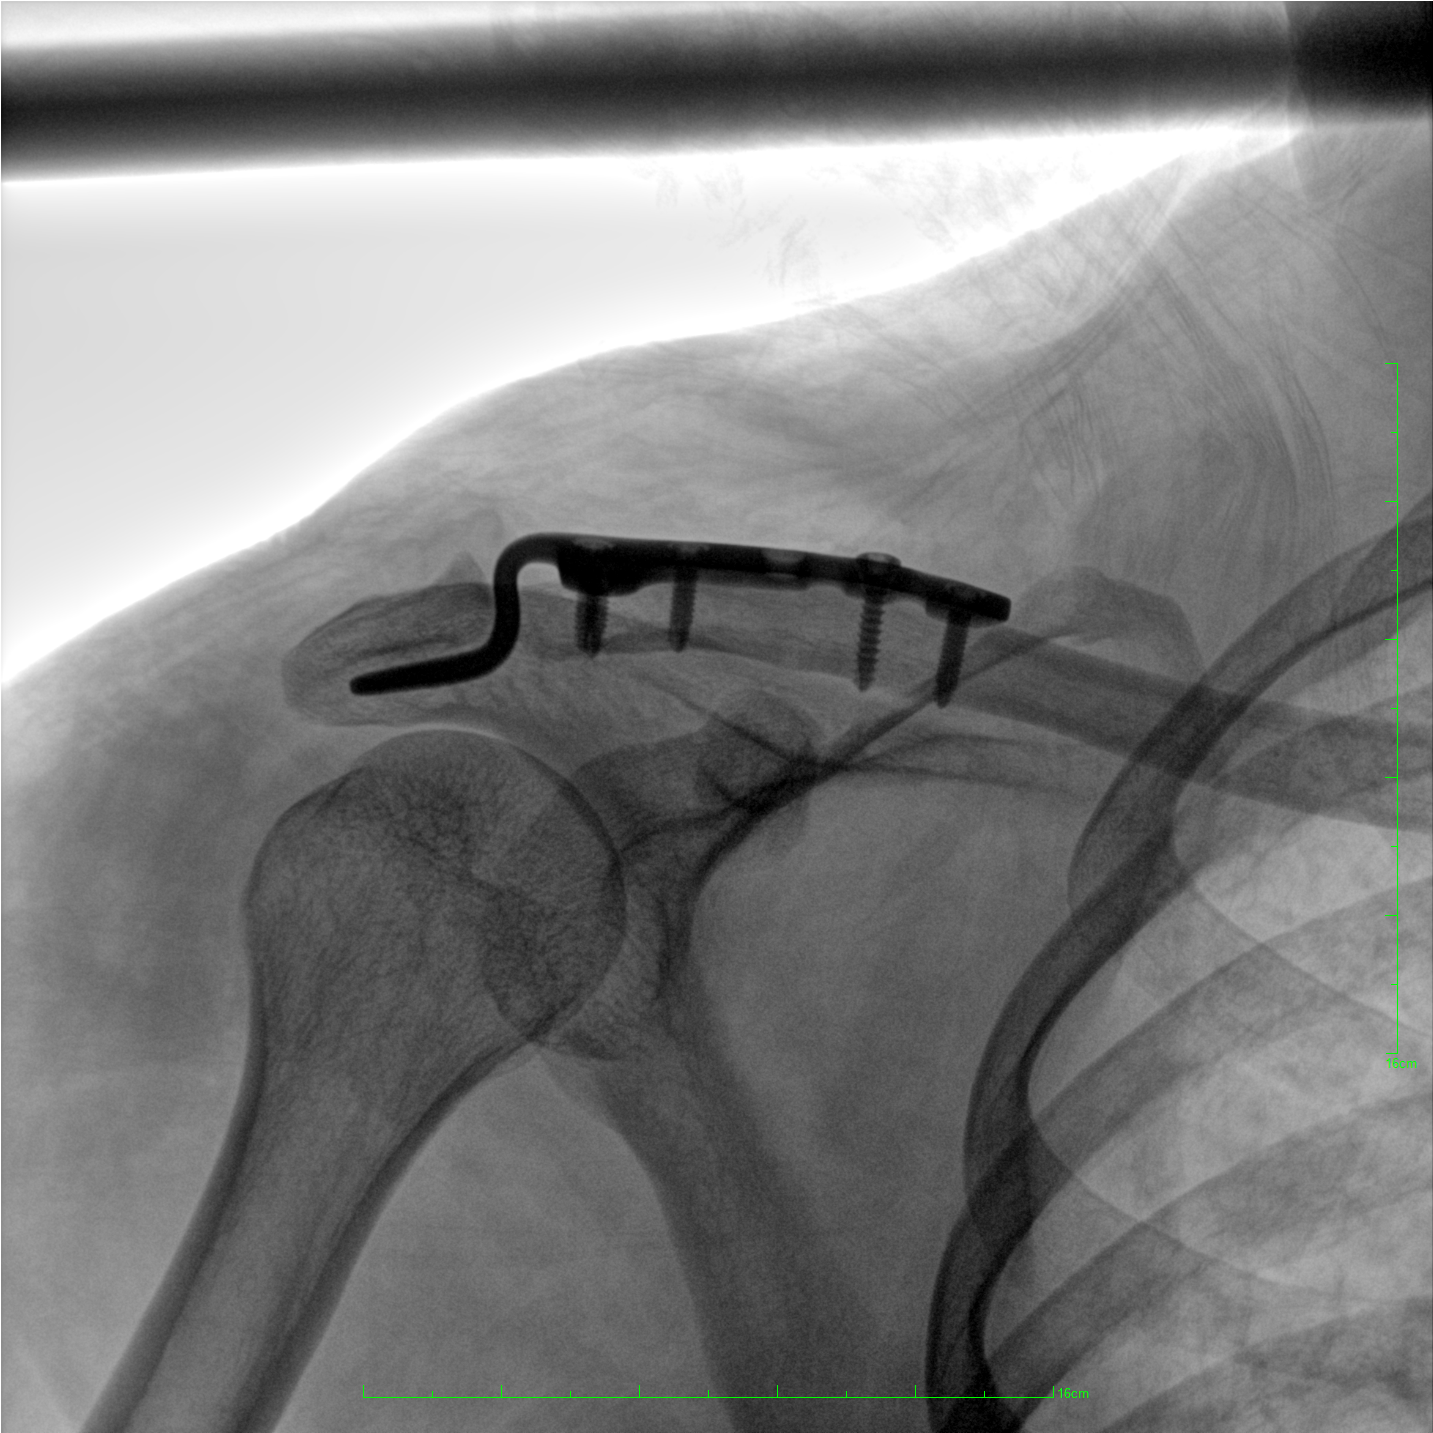

術(shù)中三維成像和橫斷面圖像提供多角度的手術(shù)診斷信息,輔助醫(yī)生進(jìn)行術(shù)中評(píng)估判斷,諸如骨折復(fù)位情況和內(nèi)植入螺釘?shù)某叽绾臀恢?,輔助手術(shù)更好地完成。

在C臂掃描過(guò)程中,始終保持拍攝主體處于射線(xiàn)束的中心,避免了序列圖像采集過(guò)程中的橫縱方向運(yùn)動(dòng),減少相對(duì)運(yùn)動(dòng)造成的運(yùn)動(dòng)偽影。